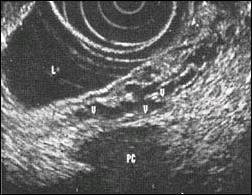

The endoscopic identification of pancreatic pseudocysts may be difficult if there is no protrusion of the gastric or duodenal wall. In these cases EUS-guided drainage of pseudocyst is precise and can be performed even if the cyst dose not produce an endoscopic appear bulge(5,6) (Fig. 6). The advantages of this diagnostic procedure are: 1) exact localization of the pseudocyst. 2) identification of retrogastral blood vessels (Fig.7). 3) differential diagnosis between malignant and benign cystic lesions and intracystic haemorrhage. 4) precise punction with the cystotom under EUS-control (Fig.8). 5) contrary to ERP, riskless use of EUS in case for acute pancreatitis. 6) measurement of the thickness of the cystic wall.

Fig. 6. EUS-document of corectly implanted guide and

nasocystc catheter in a pancreatic pseudocyt

Fig. 7. Endoscopic ultrasonographic representation of

intra or extramural venectasia and search

for an avascular area to allow safe puncture.

V : varix, PC : Pancreas cyst, L : Lumen